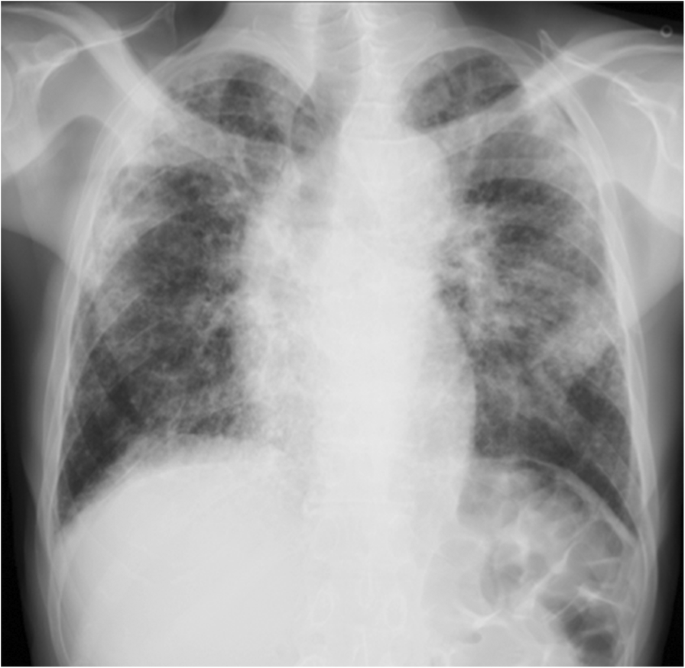

On presentation, the patient was fully conscious with a height of 160 cm, a body weight of 47 kg, body temperature of 36.8 °C and percutaneous oxygen saturation (SpO2) of 94% on room air. Physical examination revealed fine crackles upon auscultation, especially on the bilateral upper lung areas. Otherwise, there were no abnormal physical findings. Laboratory data demonstrated elevated serum levels of Krebs von den Lungen-6 (KL-6; 1631 U/mL) and surfactant protein D (SP-D; 157.3 ng/mL), compared to normal values of < 500 U/mL and < 110 ng/mL, respectively. Antinuclear and autologous antibodies were all negative. Chest X-ray showed linear and reticulonodular shadows with marked bilateral pleural thickening in the upper lung fields (Fig. 2). Chest CT indicated bilateral dense sub-pleural consolidation, bronchiectasis and ground glass opacities in the bilateral upper lobes (Fig. 3). Pulmonary function tests showed a restrictive disorder: vital capacity (VC) of 1.12 L (34.6% of predicted), forced expiratory volume in 1.0 s (FEV1) of 0.99 L (42.5% of predicted), FEV1/FVC (forced vital capacity) of 74.4% and total lung capacity (TLC) of 2.48 L (47.7% of predicted). The patient was unable to perform the diffusion test correctly. TBLB was performed with bronchoscopy to get tissue samples of the right upper lobe (B2). Bronchoalveolar lavage fluid, obtained by infusing 150 mL of saline, revealed a total cell count of 6.0 × 104/mL, comprised of 3% lymphocytes, 1% neutrophils, 2% eosinophils and 94% macrophages (Cluster of Differentiation, CD 4/8 ratio of 2.31), which was in the normal range. The biopsied specimen had fragments of bronchiolar wall with infiltration of lymphocytes in interstitial spaces; unfortunately, it did not contain alveolar tissue. A surgical diagnostic procedure was avoided due to the patient’s critical respiratory condition and instead, elemental analysis was performed on the existing specimen obtained by TBLB. The content of aluminum and other particles were measured in the TBLB sample.

In our case, the biopsied specimen contained only bronchiolar walls without alveolar tissue, and so did not allow histological confirmation of PPFE. Chest CT indicated upper lobe predominant pleural thickening with pulmonary fibrosis, bronchiectasis and pulmonary shrinkage, which was compatible with radiological findings for PPFE [1, 2]. On the other hand, there were features inconsistent with PPFE, including the presence of lower lobe as well as upper lobe fibrosis and lesions deep inside the lung were observed in addition to sub-pleural fibrosis. Furthermore, typical chest CT images of PPFE reveal a clear demarcation between the abnormal and normal parts of the lung [5], while it was ill-defined in the present case. It is controversial whether reticulonodular shadows in deep areas of the lung are an element of PPFE.